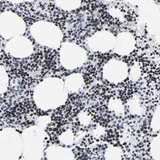

Immunohistochemistry (Formalin/PFA-fixed paraffin-embedded sections) - Anti-ZNF589 antibody (AB121173)

• IHC-P

Unknown

ab121173 at 1/100 dilution staining ZNF589 in Paraffin-emebedded Human bone marrow tissue by Immunohistochemistry.